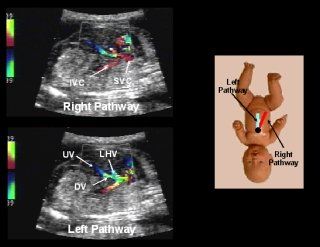

Animal studies have suggested that blood from the ductus venosus preferentially enters the left atrium through the foramen ovale, with little or no mixing occurring within the right atrial chamber 13 . This results in streaming of oxygenated blood into the left atrium, avoiding mixing with deoxygenated blood from the right atrial chamber. Kiserud et al recently suggested, however, that there appeared to be controversy in the literature because several investigators have suggested that, in the human fetus, blood first enters the right atrium, and then flows across the foramen ovale to the left atrium 14-16 . In an attempt to clarify this issue, Kiserud et al studied 103 fetuses between 15 and 40 weeks of gestation with color Doppler ultrasound 14. They reported that the segment of the inferior vena cava proximal to the right atrium contained a confluence of ‘right’ and ‘left’ pathways

The right pathway contained blood originating from the inferior and superior vena cava and the right hepatic vein, while blood from the left pathway originated from the ductus venosus and the left hepatic vein. Although both right and left pathways become confluent upon entrance into the terminal portion of the inferior vena cava, Kiserud et al were able to demonstrate preferential streaming, the right pathway directing blood to the right atrium; the left pathway directing blood to the left atrium through the foramen ovale